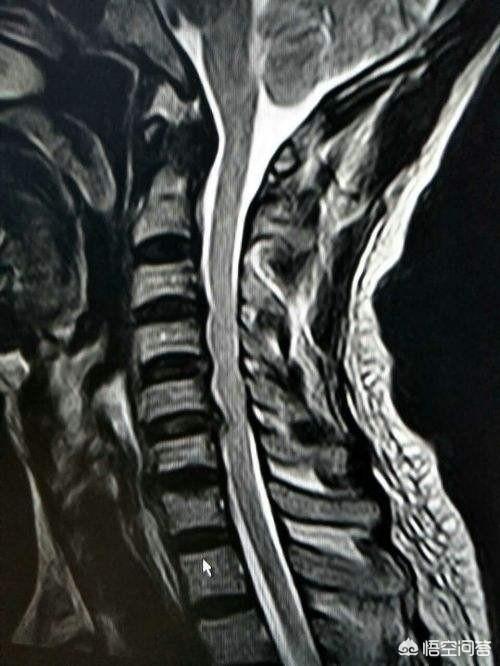

神経根を圧迫する頚椎椎間板ヘルニアは肩の痛みの原因になる

頚椎に鍵盤ヘルニアがあったり、骨髄が形成され圧迫する骨棘がある場合。肩の痛みは、神経根が定位置にない場合に起こる。この痛みの特徴は、電気ショックのようなピンと刺すような痛みがほとんどで、一般的に肩の動きとは無関係である。つまり、この痛みは肩の動きの角度に関係なく存在するということです。むしろ、この痛みと頚椎の活動には関係があるかもしれません。例えば、頚椎を過度に後傾させたり、頭を前に反らせたりすると、神経根が刺激され、痛みが悪化する可能性があります。

簡単に言えば、痛みは肩に現れるが、問題は頸椎にある!

頚椎が肩の痛みを引き起こしていると疑われる場合は、頚椎の検査を行う必要がある。頚椎MRI頚椎椎間板ヘルニアや骨構造の異常が神経拘縮を引き起こしていることを確認し、肩や上肢の筋力低下を伴う場合は、以下のような処置が必要な場合もある。筋電図この検査によって、神経が損傷しているかどうかが明らかになる。治療方法鍼灸を行う、または受けるを達成するために取り組むべき最も重要な問題を以下に挙げる。曳く痛みがひどい場合は経口鎮痛・抗炎症薬このような痛みのほとんどは神経根の浮腫につながるため、内服することが可能である。抗浮腫薬、また、経皮的電気神経刺激などの理学療法を受けることもできますが、通常は体系的な治療で緩和されます。この期間は急性期で1~2週間、徐々に緩和するのに3ヶ月ほどかかりますのでこの種の問題は、物事をゆっくりと進めることが重要なのです。。

頚椎症

左肩の痛みの原因となる頚椎症には、頚椎症と神経根症の2種類があります。頚椎症は、首の痛みや不快感として現れ、動きが制限され、肩の後ろに放散することがあります。神経原性頚椎症は、主に上肢のしびれ、脱力、痛みを引き起こし、肩の痛みや不快感も引き起こします。

6.頚椎症

頚椎症は、一般に頚肩腕症候群と呼ばれる肩の痛みを引き起こす可能性もあります。最も一般的なのは、頚部神経根が圧迫される症状で、関節機能に制限はなく、手足のしびれや脱力などの症状を伴う、それほど強くない肩の痛みを引き起こします。

例えば、神経根を圧迫している頚椎椎間板ヘルニアが肩の痛みや脱力を引き起こすこともありますし、頚神経叢神経が瘢痕組織の増殖によって神経を圧迫しているためにこのような痛みを引き起こすこともあります!